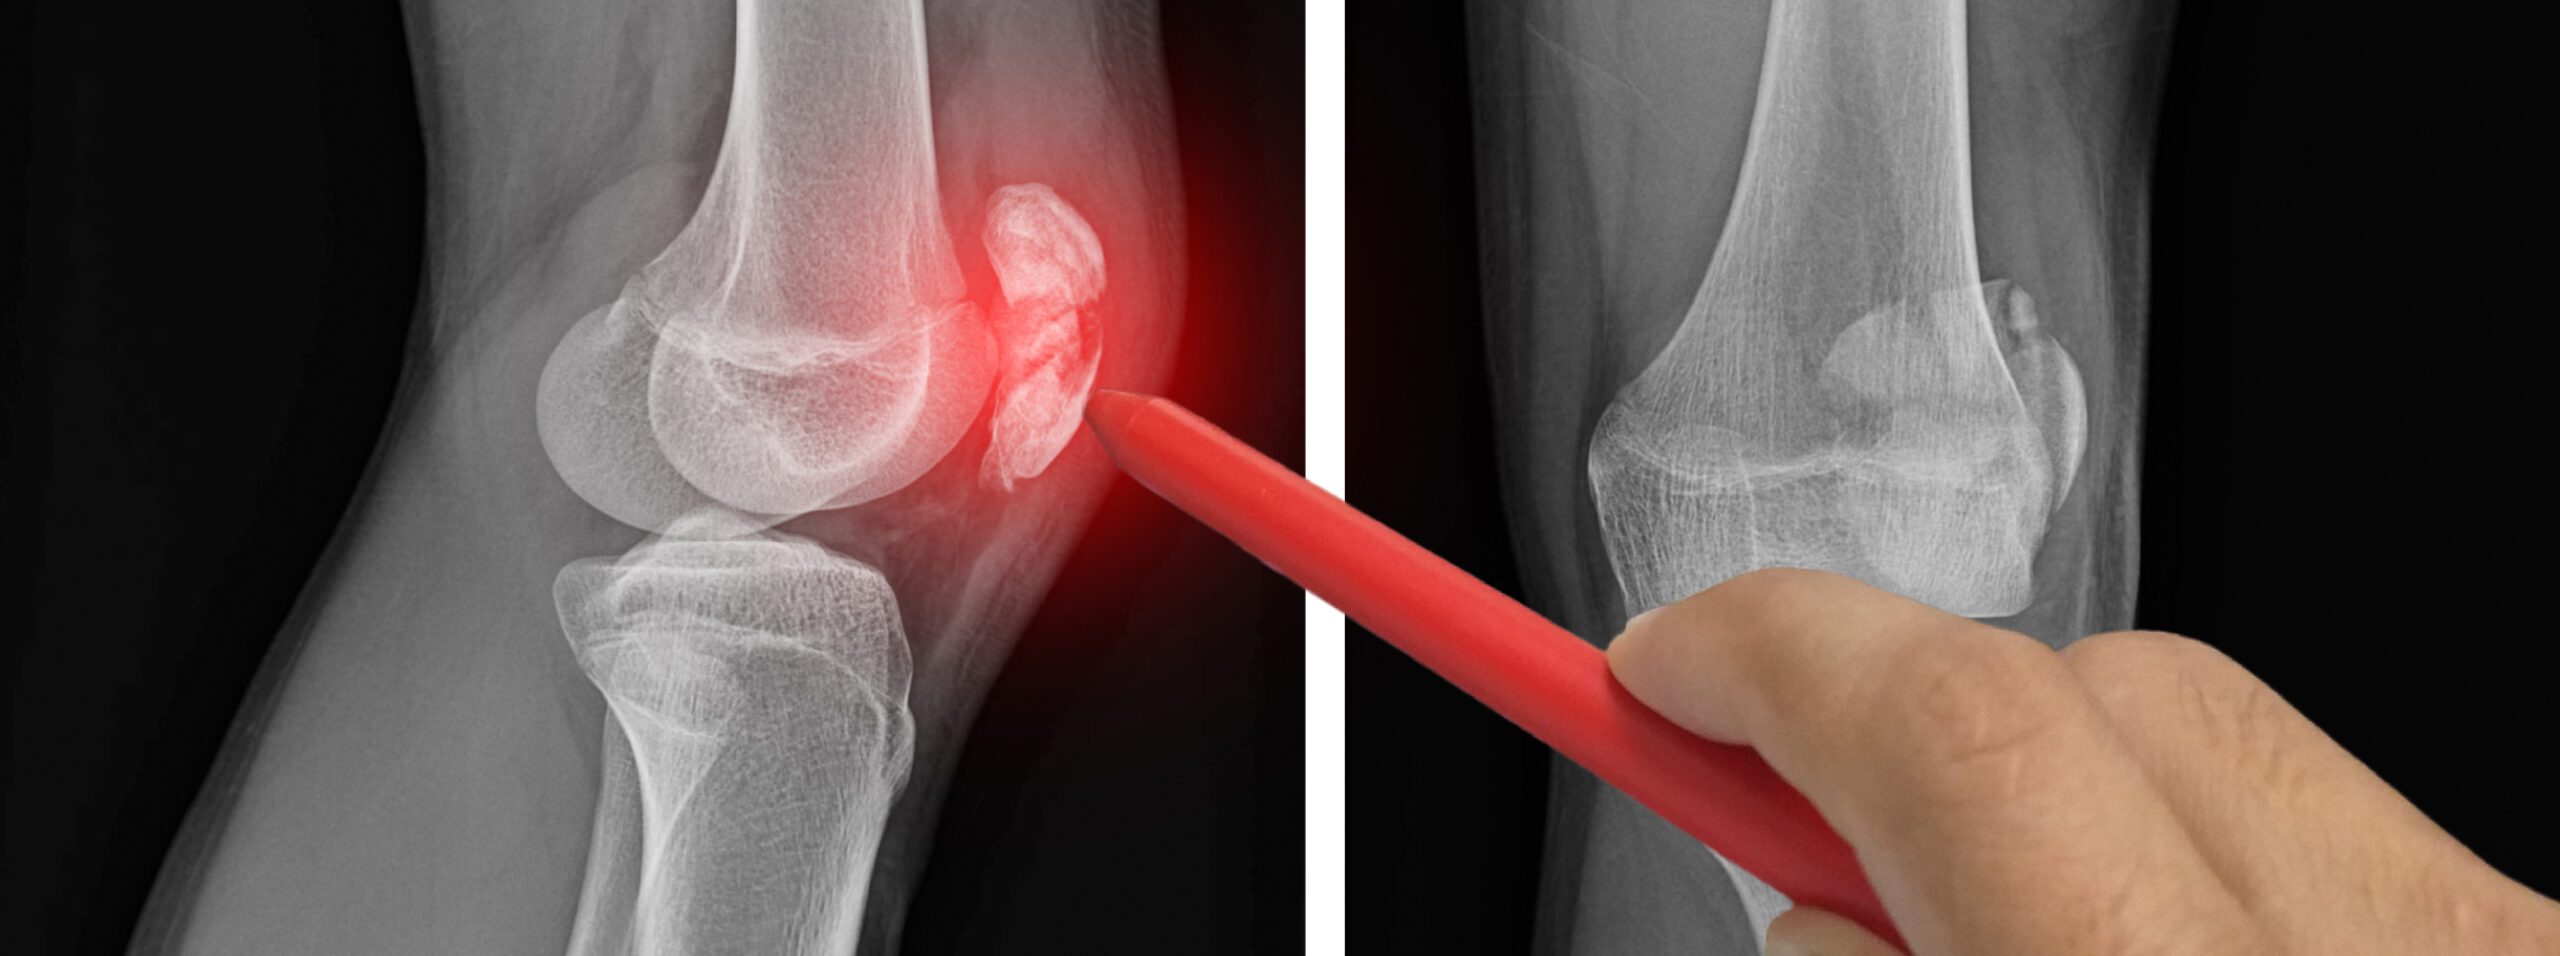

Ce geste est indiqué dans de nombreuses pathologies :

• arthrose (genou, hanche, épaule, cheville…)

• tendinites, bursites, capsulites

• lombalgies, sciatiques, ou douleurs liées à un conflit articulaire